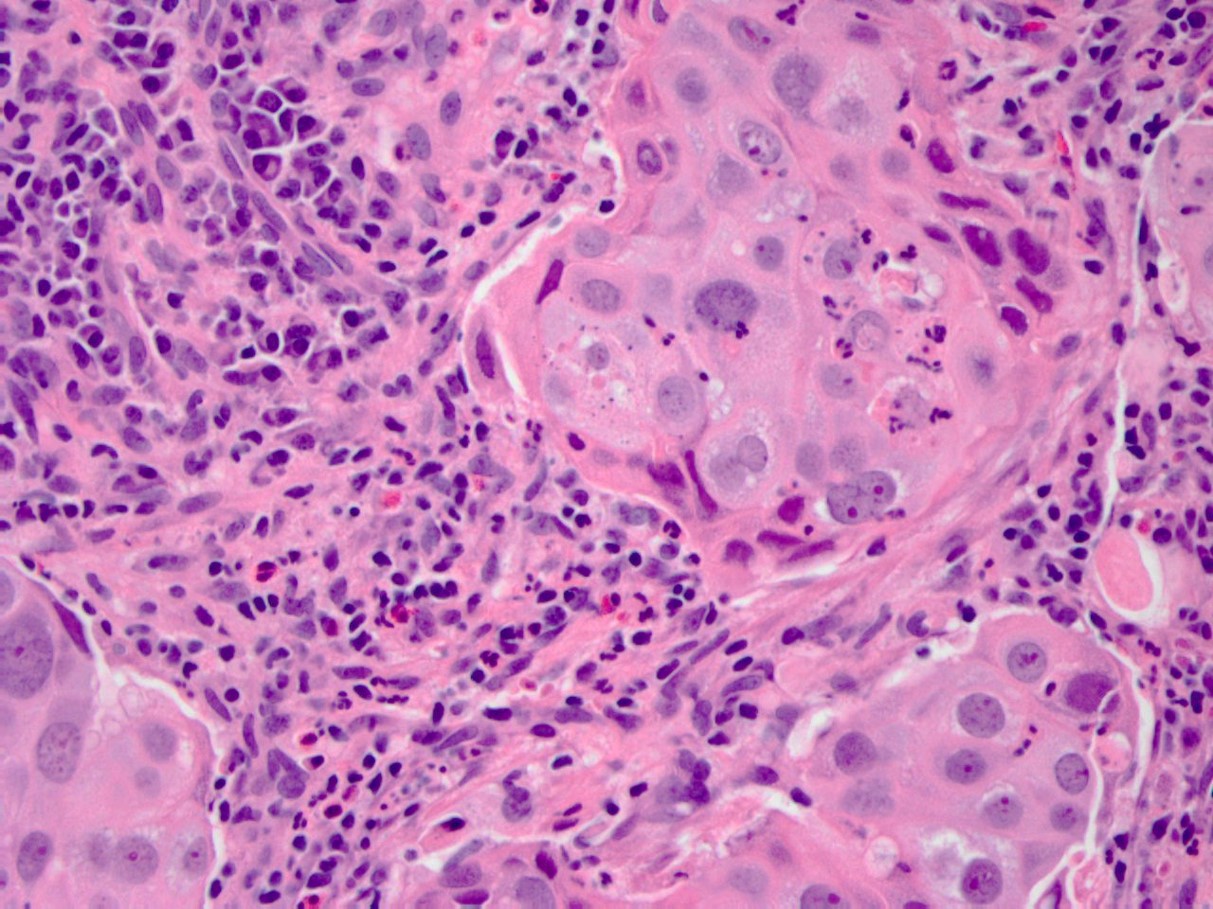

The correct diagnosis is B, glassy cell carcinoma.

The median age for this carcinoma is 45 years old and presents as a rapidly growing cervical mass and a barrel shaped cervix. The histology presents as a poorly differentiated variant of adenosquamous carcinoma characterized by large cells with cytoplasmic margins, “ground glass” appearing eosinophilic cytoplasm, large nuclei, prominent nucleoli and eosinophilic infiltrate in the surrounding stroma. Notable IHC includes positivity for MUC2 (intestinal type mucin). The etiology stems from HPV-18 infection. Patients tend to do poorly, though radiotherapy is associated with decreased risk of recurrence.